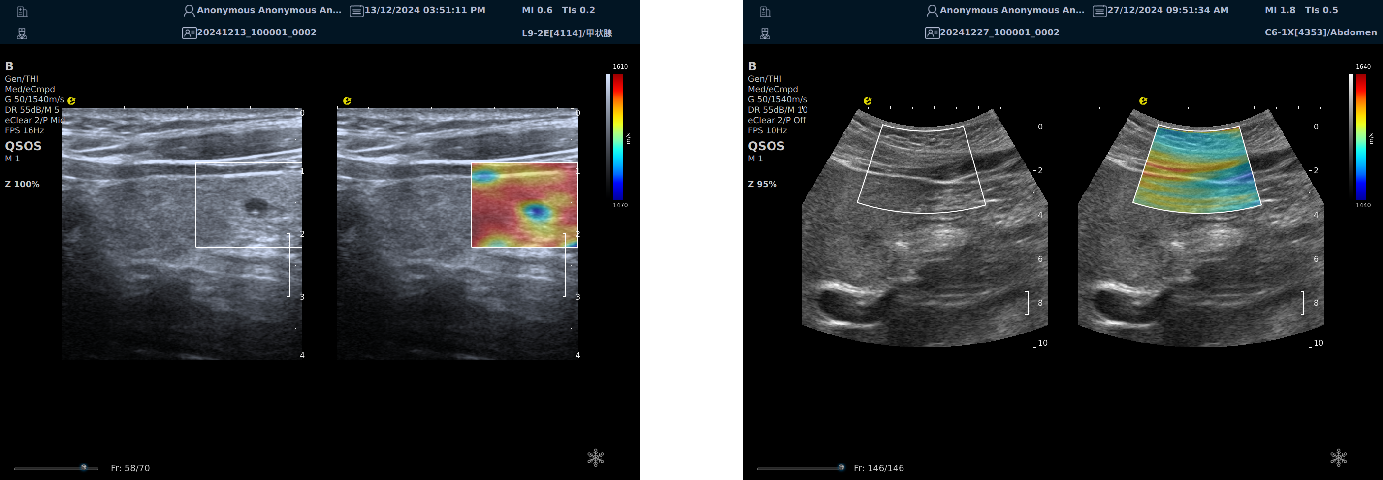

image.png

左图病例所示:

钼靶阴性,B型发现非肿块病变

剪切波弹性成像见明确的硬度增高区域。

穿刺及手术病理结果:浸润性导管癌(IDC)

非肿块型病变:B型图像无法确认病变范围,E成像帮助发现异常区域和评估